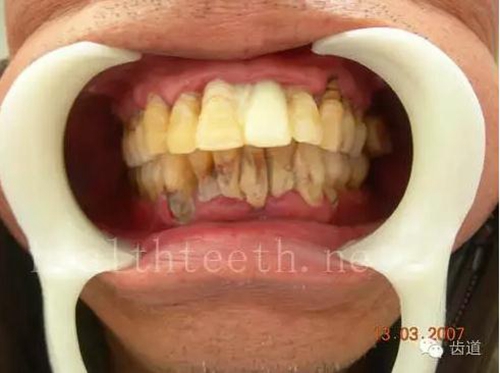

全口牙牙齦炎,出血嚴(yán)重